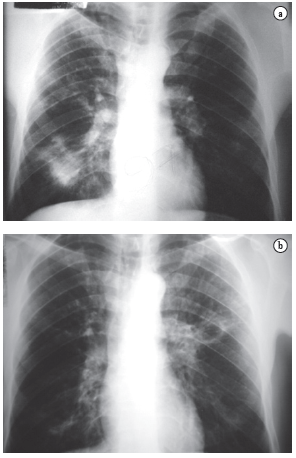

As queixas clínicas, os dados de exame físico e as alterações radiológicas apresentadas por esses doentes, na maioria das vezes, não permitiram a diferenciação segura entre as duas doenças (Figuras 2, 3 e 4).

A PCM acomete muito mais o sexo masculino (15:1), sendo a maioria dos pacientes formada por lavradores ou ex-lavradores com idade entre 30 e 50 anos. Comumente são oligossintomáticos, com poucos achados de exame físico, podendo, no entanto, apresentar exuberantes alterações radiológicas torácicas tanto na radiografia simples quanto na tomografia computadorizada de alta resolução.(11-15)

O acometimento pulmonar é geralmente bilateral, com predomínio nos campos médios e regiões medulares.(16,17)

Por sua vez, a TB acomete ambos os sexos em qualquer idade, com a maioria dos pacientes se apresentando sintomáticos, com exame físico comprometido e alterações radiológicas, em geral, de predomínio em segmentos superiores e posteriores, podendo também ser bilaterais.